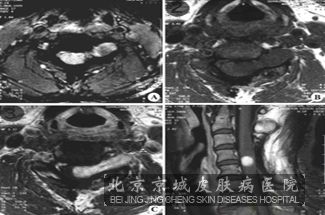

北京京城皮肤医院指出:神经纤维瘤的患者一般会有50 的患者会有神经系统病变。此损害主要就是中枢周围神经肿瘤压迫引起,再有就是胶质*增生、血管增生和骨骼畸形所致。主要损害为颅内肿瘤、椎管内肿瘤、周围神经肿瘤等病变。